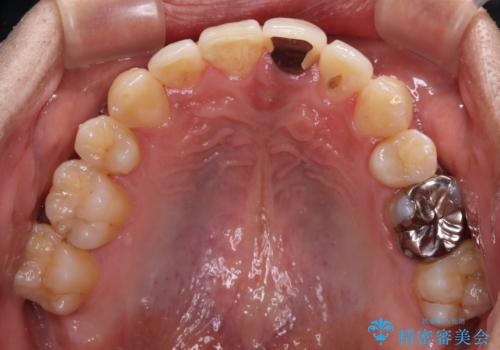

- 下顎の八重歯を気にして来院された患者様です。

左下以外、3本の第一小臼歯が既に抜去されており、左下は八重歯になっている状態でした。

左下の八重歯は手前に傾斜していたため、インビザラインによる抜歯矯正が可能と判断し、後方にある第一小臼歯を抜歯してインビザラインにて矯正治療を行うこととしました。